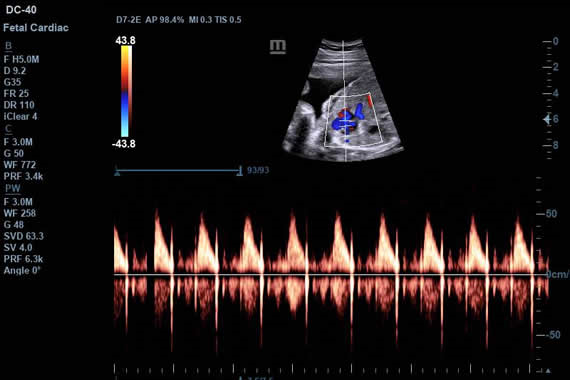

Клинические изображения

- D7-2E - Конвексный датчик объёмного сканирования в реальном масштабе времени (необходим модуль 4D)